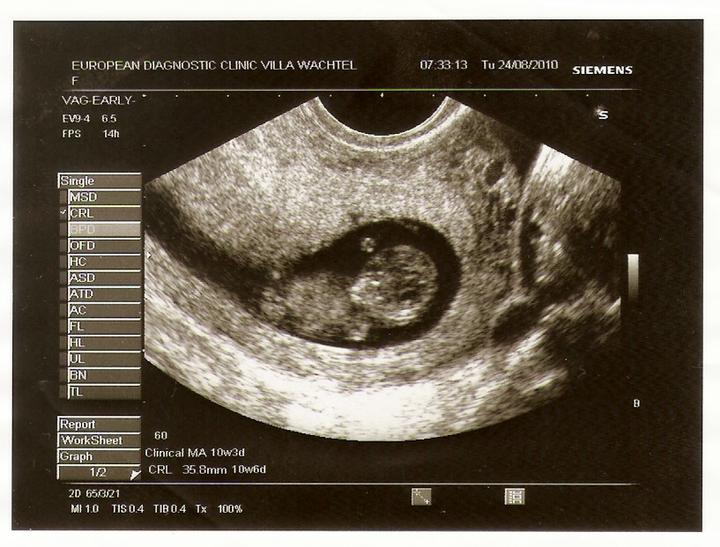

24.8.2010 kontrola u paní doktorky v 11. týdnu - vše je v pořádku, měříme 3,58 cm a dostali jsme novou fotečku.